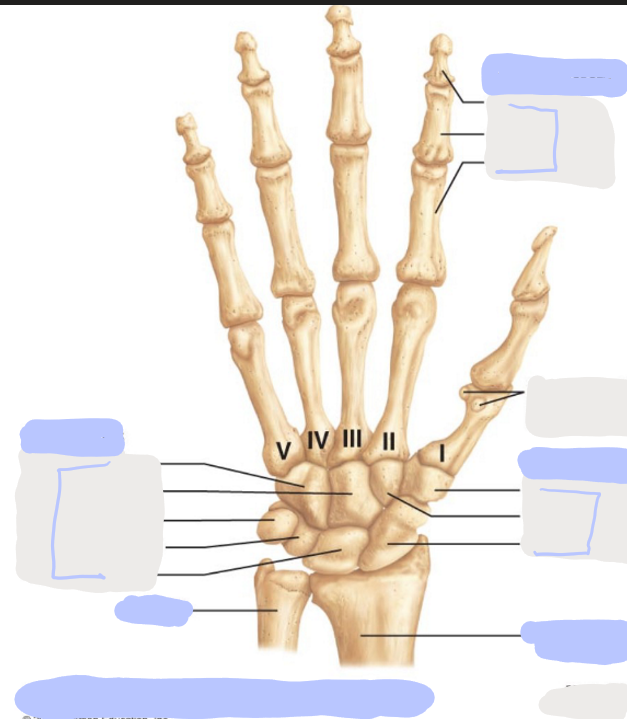

What is this picture of?

Posterior View of the Right Hand

What is here?

Where is the Ulna?

What is here?

Where is the Radius?

What is here?

Where are the Metacarpals?

What is here?

Where are some of the Carpals?

What is here?

Where are some of the Carpals?

How many carpals are there?

8

How many metacarpals are there?

5

How many phalanges are there?

14